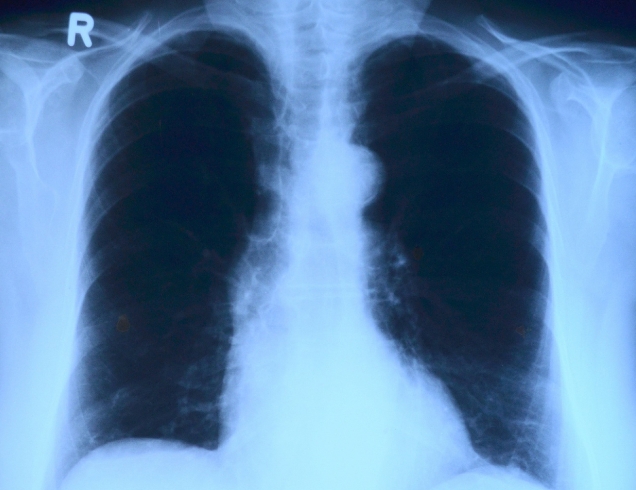

호흡기질환

호흡기 질환은 바이러스나 세균의 감염, 흡연,유전등 다양한원인으로 발생됩니다.